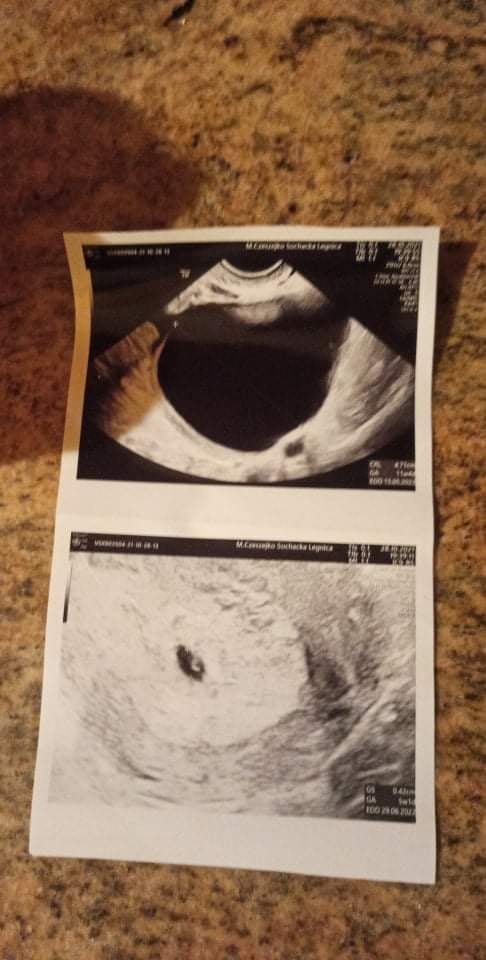

Już wstawiłam gdzieś to zdjęcie. To był chyba 5 tydzień, na górze torbiel, która była chyba na prawym jajniku. Miałam do końca ciąży, później na kontroli już jej nie było.Dzięki za informacjęrozumiem, że miałaś ja przez całą ciążę i dopiero po porodzie się wchloneła?